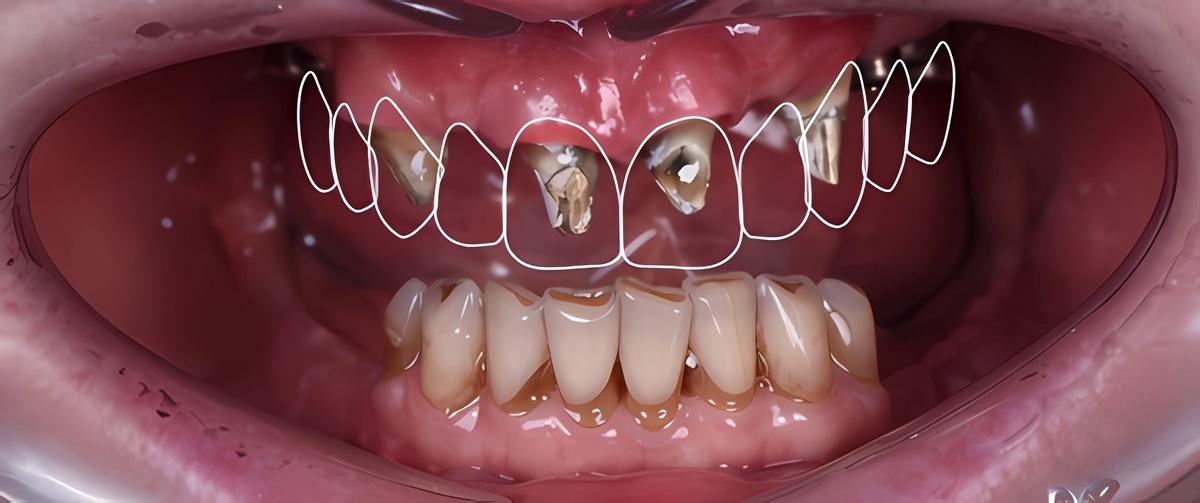

Оставим за скобками мероприятия по изготовлению временных конструкций, служивших не более, чем небольшим утешением нашей героине. Основная работа началась после имплантация зубов верхней челюсти, по традиции, с моделирования будущей улыбки на экране монитора (DSD)

Первая примерка :

Верхняя челюсть: 2 мостовидных протеза в жевательных отделах с опорой на 3 имплантата и мост на 6 единиц с опорой на 4 собственных зуба